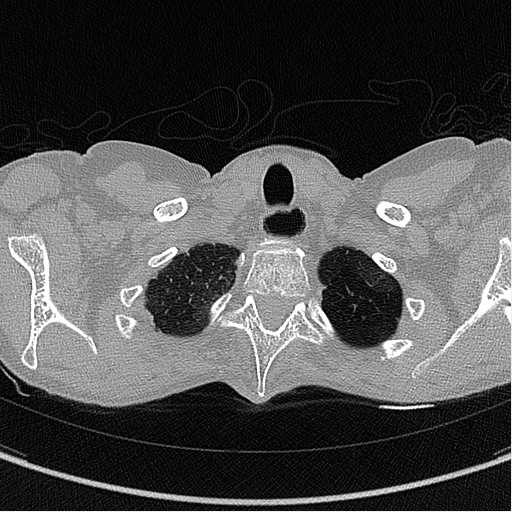

Example of CT Scan

The images below are examples of different acquisition for a sample subject that did a full exam.

exemple exemple

Expiration acquisition without injection. Left mediastin reconstruction, rith parenchyme reconstruction.